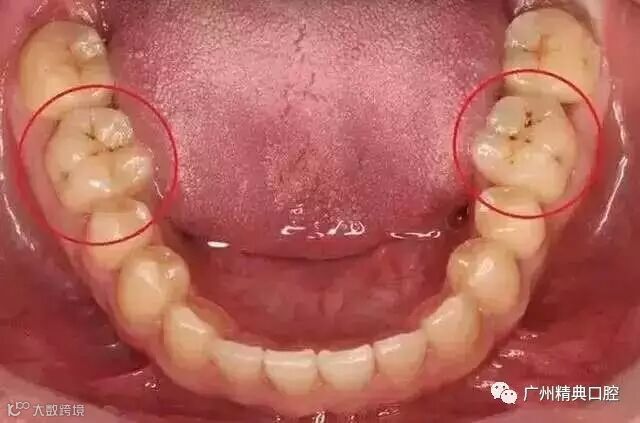

2牙齿出现了或深或浅的龋坏

牙齿出现龋坏,从外面看就表现为一个黑点,通常位于窝沟点隙(牙面上点状或线状凹陷)。龋齿的罪魁祸首是口腔中的某些细菌,但它们破坏牙齿也是需要时间的,从初期的变色到最终形成龋洞,通常需要1年半到两年。在此期间,我们多留心自己的牙齿,完全可能把龋坏扼杀在萌芽阶段。如何才能及时发现这种隐匿的蛀牙呢?找位好牙医,半年检查牙齿!